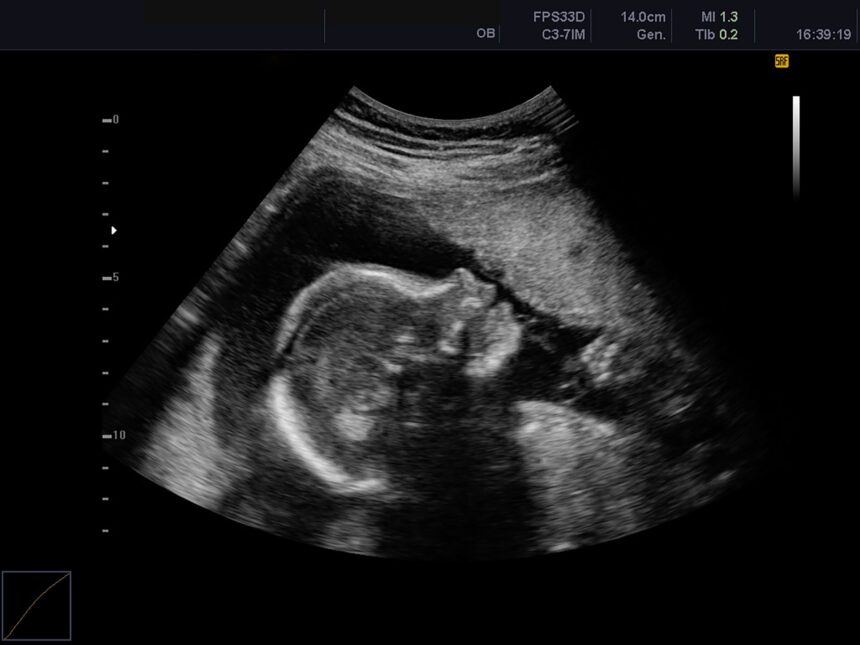

„Copiii de piatră” reprezintă o strategie extrem de rară de protecție a corpului uman, apărând în condiții neobișnuite și adesea nefaste. Acest fenomen se poate manifesta în urma unei sarcini abdominale, atunci când un ovul fertilizat începe să se dezvolte în afara uterului, ceea ce este extrem de periculos.

Într-un procentaj mic de astfel de sarcini, atunci când fătul moare, corpul mamei reușește să-l protejeze printr-un proces de calcificare, transformându-l într-un „copil de piatră”. Deși termenul sugerează piatră, în realitate este vorba despre un proces prin care organismul impregnează fătul cu calciu, principalul component al oaselor, prevenind astfel riscul de sepsis.

Termenul medical pentru un făt calcificat este lithopedion, derivat din greaca veche, însemnând „copil de piatră”. Acest fenomen este extrem de rar, fiind documentat doar de câteva sute de ori în întreaga istorie a omenirii. Cel mai adesea, lithopedionul rămâne nedetectat timp de ani sau chiar decenii, fiind descoperit adesea după menopauză sau, în unele cazuri, post-mortem.

Se estimează că lithopedionul apare în 1,5-1,8% dintre sarcinile abdominale. Deși sarcina abdominală este o formă de sarcină ectopică, în care embrionul se implantează în afara uterului, cazurile de lithopedion documentate sunt mult mai puține, cu doar aproximativ 300 de cazuri raportate în ultimele 400 de ani.

„Copiii de piatră”, cunoscuți și sub denumirea de lithopedion, reprezintă un fenomen rar care se formează în corpul uman. Acesta apare în cazul în care resturile fetale rămân în abdomenul unei femei, având potențialul de a trăi decenii fără ca aceasta să fie conștientă de prezența lor.

Un raport din anul 2000 a documentat un astfel de caz la o pacientă de 80 de ani. De asemenea, în 2014, un alt raport a descris o pacientă de 77 de ani care credea că nu fusese niciodată însărcinată, dar care avea un lithopedion. În 2016, un caz similar a fost descoperit post-mortem la o femeie de 87 de ani.

Experții subliniază că, datorită standardelor tot mai ridicate în îngrijirea ginecologică și obstetrică, acest fenomen devine tot mai rar. Sarcinile abdominale sunt acum identificate mai devreme și tratate înainte ca fătul să ajungă la stadiul de calcificare.